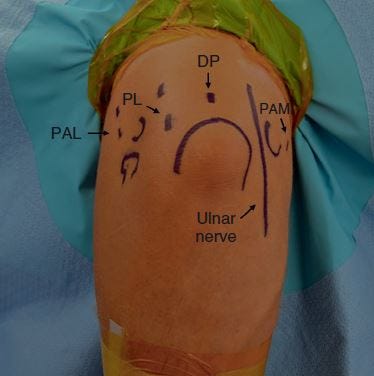

It is absolutely necessary to make an accurate diagnosis, start by knowing what to look for. Figure 2 shows the example x-rays of a bone chip. Once properly diagnosed, treatment will depend on the severity of the symptoms. Some players can get through the season with anti-inflammatory medication and even a cortisone injection. Other players will experience pain to a debilitating degree, and require surgery. Fortunately, bone chips can be removed arthroscopically, and as you can see in figures 3, 4, and 5 and the pain related to the bone chips is eliminated.